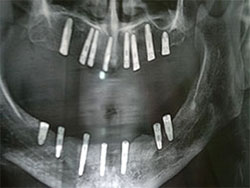

Full Mouth Implant Case